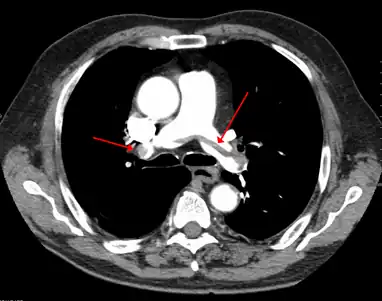

- A CT image with red arrows indicating PE (grey) in the pulmonary arteries (white)

A pulmonary embolism (PE) occurs when a blood clot from a deep vein (a DVT) detaches from a vein (embolizes), travels through the right side of the heart, and becomes lodged as an embolus in a pulmonary artery that supplies deoxygenated blood to the lungs for oxygenation.[28] Up to one-fourth of PE cases are thought to result in sudden death.[12] When not fatal, PE can cause symptoms such as sudden onset shortness of breath or chest pain, coughing up blood (hemoptysis), and fainting (syncope).[29][30] The chest pain can be pleuritic (worsened by deep breaths)[29] and can vary based upon where the embolus is lodged in the lungs. An estimated 30–50% of those with PE have detectable DVT by compression ultrasound.[30]